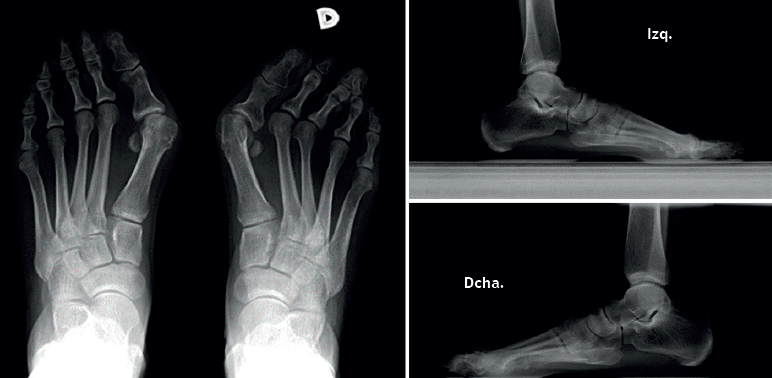

Para realizar una correcta evaluación radiológica se deben realizar al menos 2 proyecciones en carga, una proyección dorsoplantar y una lateral del pie (Figura 2).

Figura 3. Ejemplos de hallux valgus intervenidos en nuestro centro: A: pie izquierdo pre-intervención quirúrgica (IQ); B: pie izquierdo post-IQ; C: pie derecho pre-IQ; D: pie derecho post-IQ.